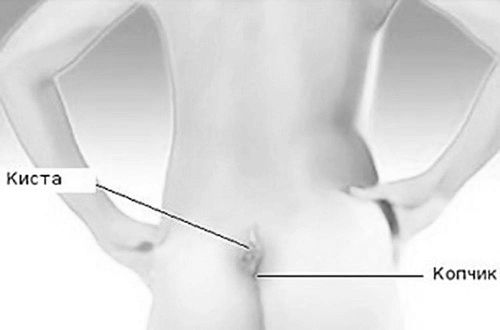

Що таке кіста куприка?

Кіста синуса, розташована на сім сантиметрів вище куприка. Небезпечне захворювання, яке проявляється на пізніх стадіях, що ускладнює лікування і вимагає хірургічного втручання